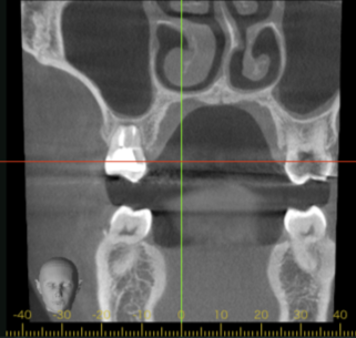

初診時CT画像

初診時デンタルX線写真とCT画像。

根管外に不透過像とそれを取り囲む透過像を認める。

コアを除去すると、分岐部へつながるパーフォレーションを認めた。

これが排膿の原因であったため、保存は困難と判断した。